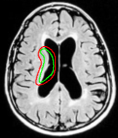

Refer to captionRefer to captionRefer to captionRefer to captionRefer to captionRefer to captionRefer to captionRefer to captionRefer to captionRefer to captionRefer to captionRefer to caption\begin{array}[]{cc}\includegraphics[width=112.0187pt]{lv-2-init.pdf}&\includegraphics[width=112.0187pt]{lv-2.pdf}\\ \includegraphics[width=112.0187pt]{lv-3-init.pdf}&\includegraphics[width=112.0187pt]{lv-3.pdf}\\ \includegraphics[width=112.0187pt]{lv-1-init.pdf}&\includegraphics[width=112.0187pt]{lv-1.pdf}\\ \end{array}

Figure 15: Segmentation of left ventricle wall of the heart in an MR image taken from [42]. Left column shows initialization and right column shows converged result.

We next develop templates for objects with hole(s) in their structure. These templates are called ring templates. Figures 15 and 16 show examples of ring templates. The area enclosed between the red contours act as region 1subscript1\Re_{1} and the area between the green contours is region 0subscript0\Re_{0}. Figure 17 shows the construction of the ring contours. The two seemingly unconnected contours are actually one connected contour. Hence, partial derivative calculations in equation (26) are still valid.

In Figure 15, the ring template has been used for segmenting the left ventricular (LV) wall of heart in cardiac MR images. Another example is shown in Figure 16. The template used in both examples has a greater thickness in the inner ring-shaped annular region than the outer annular region. This was done to facilitate obtaining the desired object’s structural information by means of the contrast (for example, between the endocardium and the LV wall) that a good initialization can offer. Hence, while designing a template, we can incorporate prior knowledge of the object and its surroundings.